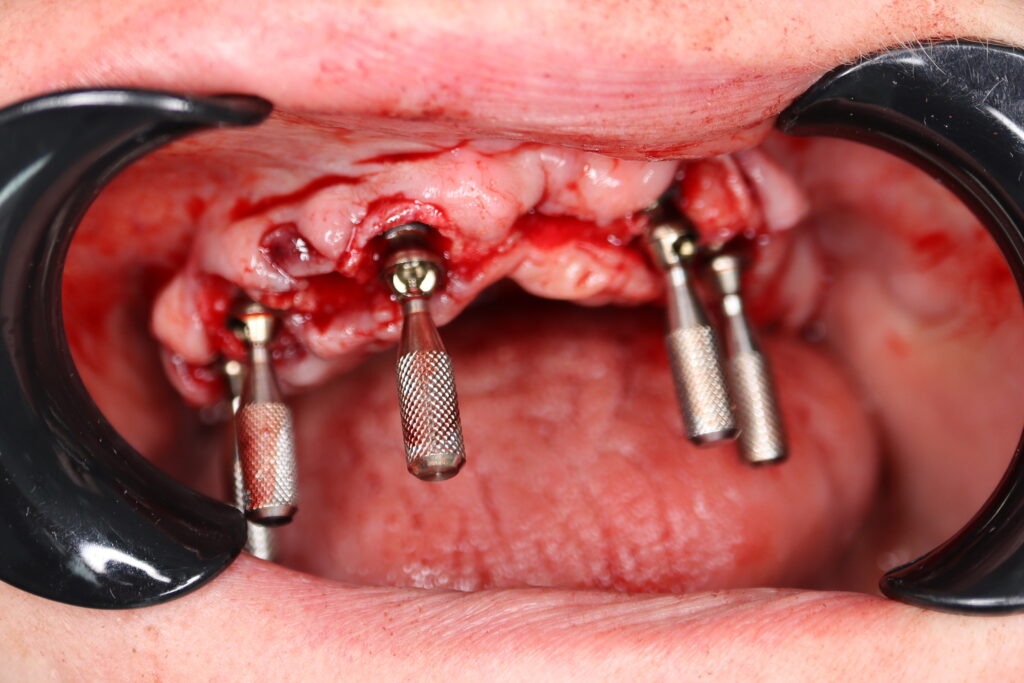

Процесс работы

Что было сделано:

На верхней челюсти были удалены зубы, которые находились в неудовлетворительном состоянии. Удалена киста в области зуба 2.1.

Установлены 5 имплантантов Megagen Anyone и сняты оттиски.

Спустя 5 дней на верхней челюсти зафиксирован протез из пластмассы, армированный металлической балкой из КХС (кобальт-хромовый сплав) с опорой на 5 дентальных имплантатов.

процесс тотальной имплантации

Это фото может содержать тяжелый для восприятия контент